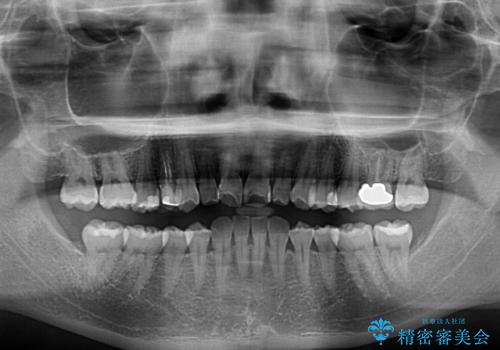

下顎前歯2本が先天欠損しており、上顎歯列に対して、下顎歯列がアンバランスに小さい状況でした。

左右上顎側切歯2本が矮小歯であるため、上顎の抜歯ではなく、IPR(歯と歯の間を削る)と歯列全体の後方移動によってバランスを整えることとしました。